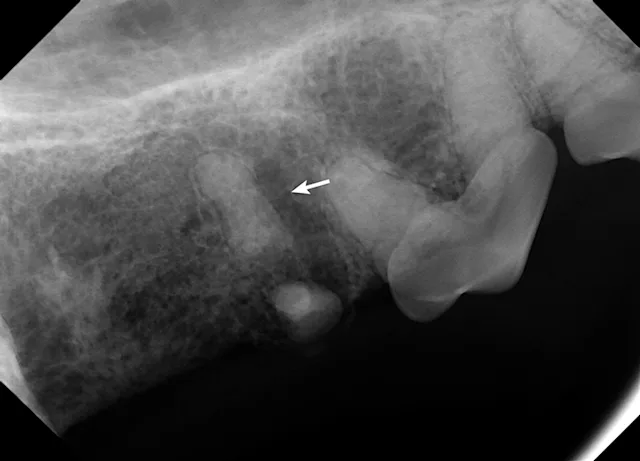

Dental radiographs confirmed the root fragment of the right maxillary fourth premolar had been retained (Figure 4). Periapical rarefaction (ie, periapical lucency) and periodontal disease of the right maxillary canine were also confirmed on radiographs; comparison with the contralateral left maxillary canine revealed that the canine tooth had been nonvital for several months, as the pulp cavity of the right maxillary canine had failed to narrow (Figures 5 and 6).1 Dental radiographs of the left maxillary fourth premolar revealed fractures of the mesiobuccal and mesiopalatinal roots in addition to advanced periodontal disease of the distal root (Figure 7).

Oral examination confirmed an unhealed extraction site of the right maxillary fourth premolar with a root fragment protruding into the oral cavity. Periodontal disease of the left maxillary fourth premolar (Figure 2) and a complicated crown fracture of the right maxillary canine (Figure 3) were also identified.